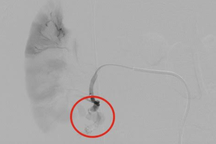

Bệnh nhân được chuyển đến phòng can thiệp mạch số hóa xóa nền (DSA) ngay sau đó để tiến hành nút mạch cấp cứu vỡ thận. Sau khoảng 1 giờ, ca nút mạch diễn ra thành công. Hậu can thiệp, bệnh nhân được chuyển khoa Hồi sức tích cực (ICU) để theo dõi và điều trị.

Bệnh nhân 24 tuổi được can thiệp nút mạch máu vỡ ở thận (Ảnh: BV).